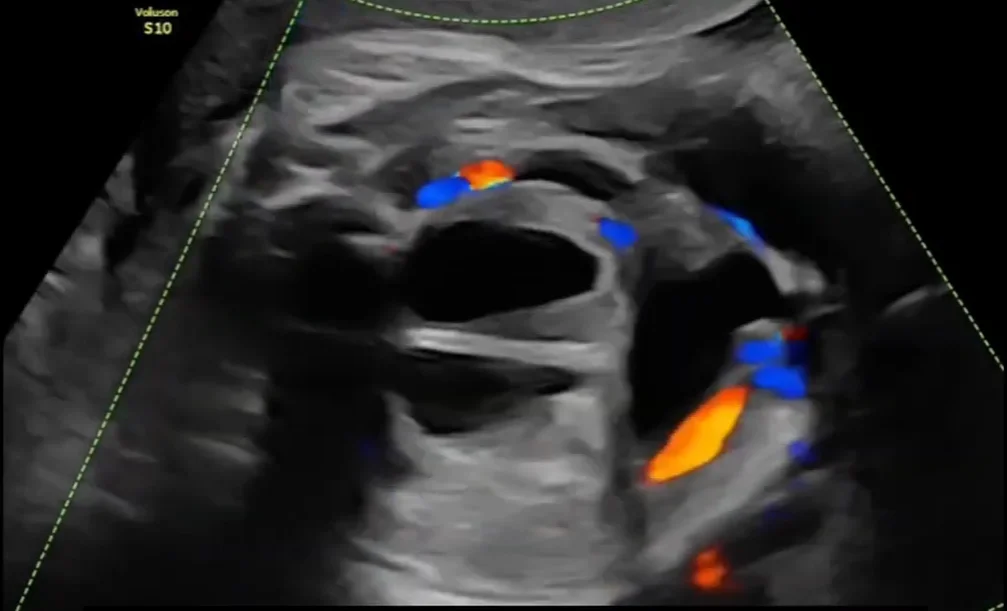

Nang buồng trứng thai nhi (Ovarian Cyst)

24/05/2026